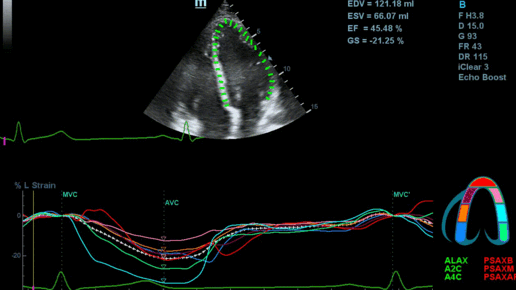

Обзор функции УЗИ: Speckle-tracking эхокардиография

Кардиомиопатии, ишемия, амилоидоз, сердечная недостаточность с сохранением фракции выброса и другие заболевания миокарда, которые длительно могут себя не проявлять, ставят сложную задачу для диагноста. Годами оставаться немыми как клинически, так и в обычной эхокардиографии. Всё изменилось с появлением технологии Speckle-tracking. Ультразвуковые приборы компании Mindray DC 8, 70, 80, Resona 6,7 оснащены данной функцией. Для использования необходим ЭКГ-канал. В чем же смысл данного технологического...